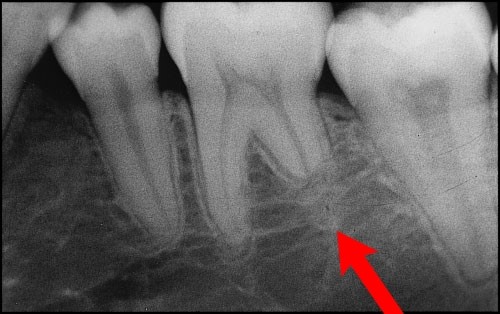

치아뿌리가 짧아짐.

교정치근흡수 (root resorption)

우리가 말하는 명언 중 하나

뿌리 깊은 나무가 바람에 아니 흔들린다.

세라믹교정을 할 때

브라켓 때문에 너무 불편한 것을 잘 알지만,

그것 때문에 원장님을 닦달하면

조금 더 세게 당겨서 하는 경우가 있는데.

그럼 치아 뿌리가 흡수되어서

짧아질 수 있어요 !

당장은 표시가 나지 않고

음식 먹는데 큰 문제가 없지만,

시간이 지나고 나이가 들면

슬슬 바퀴벌레처럼 문제가 기여 나오시기

시작한답니다.

그러니 시간에 대해서 너무 닦달하지 말고

충분한 계획을 가지고 하는 것이 좋아요!

그리고 가끔은 엑스레이를 찍어서

뿌리가 흡수되고 있는지 확인하는

꼼꼼함까지 있다면 많은 예방이 되지요 ~

물론 그런 것까지 잘 챙겨 주는 병원을

선택하는 것이 무엇보다 좋겠지요 ~

그리고

치근흡수는 정상 적으로 나타날수 있는 현상이고

1~2mm 정도는 치아 수명이나 기능에 영향을

주지 않는다고 하니 너무 민감하게 생각해서

밤잠을 못 잘 필요까지는 없어요 ~~

위 그림에서 3~4단계부터는

철사에 주는 교정력을 멈추고

원인을 찾아 보고 다시 교정을 하는 것이 좋아요 ~